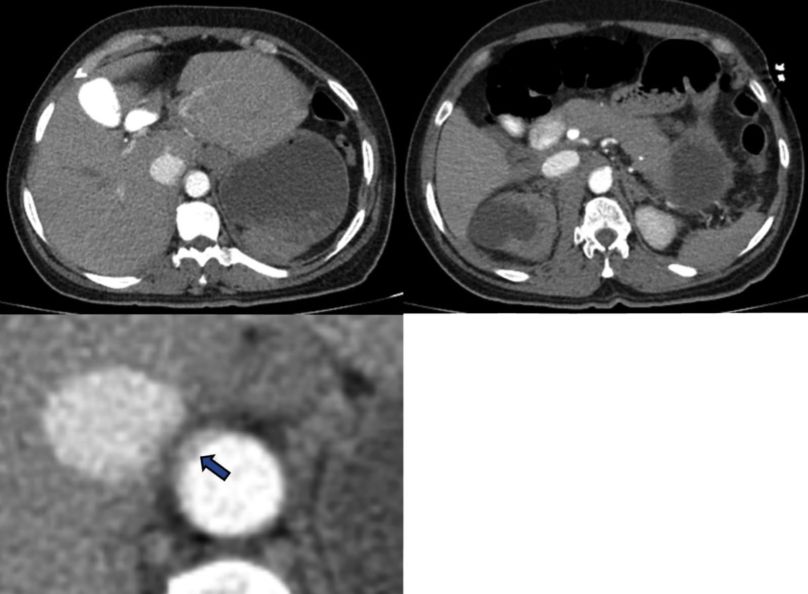

Figura 3 AngioTC de abdomen corte axial. Se observa ausencia de realce del parénquima renal derecho por hipoperfusión (flecha blanca) comparado con el riñón izquierdo (flecha azul).

Figura 4 Angiotac de abdomen en corte axial. Estriación de la grasa periaórtica y hematoma retroperitoneal (asteriscos). Opacificación de la VCI y ulcera aterioesclerótica penetrante (flecha blanca).